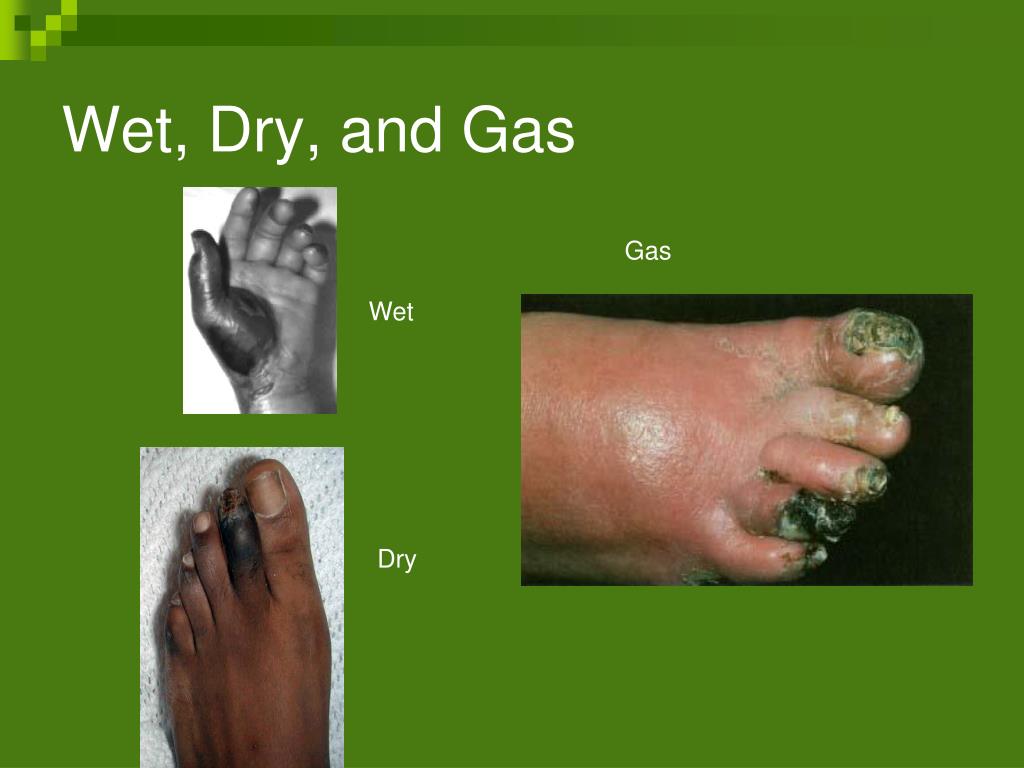

What is the difference between dry gangrene and gas gangrene?

Dry gangrene does not lead to infection. However, in the case of gas gangrene, you get a severe infection that can lead to life-threatening complic...

Can gangrene be fatal?

Gangrene can be fatal if left untreated. There are several different types of gangrene including: Dry gangrene: Tissue death results when blood flow to an area is disrupted or becomes blocked, often due to poor circulation.